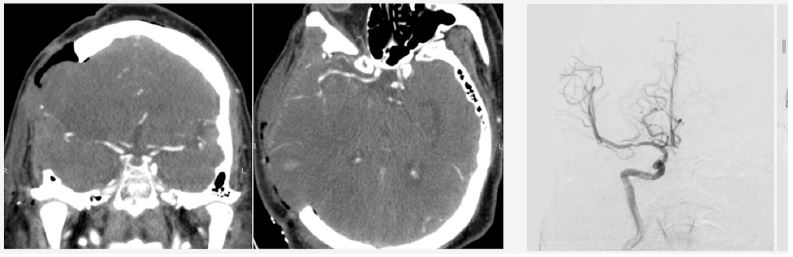

Investigations: Non-contrast CT revealed ischemic changes in the right MCA territory with an Alberta Stroke Program Early CT Score (ASPECTS) score of 6 (Figure 1). The patient was deemed ineligible for pharmacological or mechanical recanalization due to exceeding the therapeutic window.

Figure 1: Computed tomography scan upon patient admission. Evidence of ischemic stroke due to right MCA occlusion is observed.

Twenty-four hours post-admission, his neurological status worsened (GCS decreased by 4 points), and a CT scan showed a significant midline shift. A right-sided frontotemporoparietal decompressive craniectomy was performed. Postoperatively, his GCS improved to 14 and motor strength improved to 3/5 on the Lovett scale (Figure 2). A Computed Tomography Angiography (CTA) performed 48 hours after surgery showed restored flow in the M1 and distal branches of the right MCA (Figure 3). A confirmatory cerebral angiogram at two weeks demonstrated patent flow throughout the MCA distribution (Figure 4).